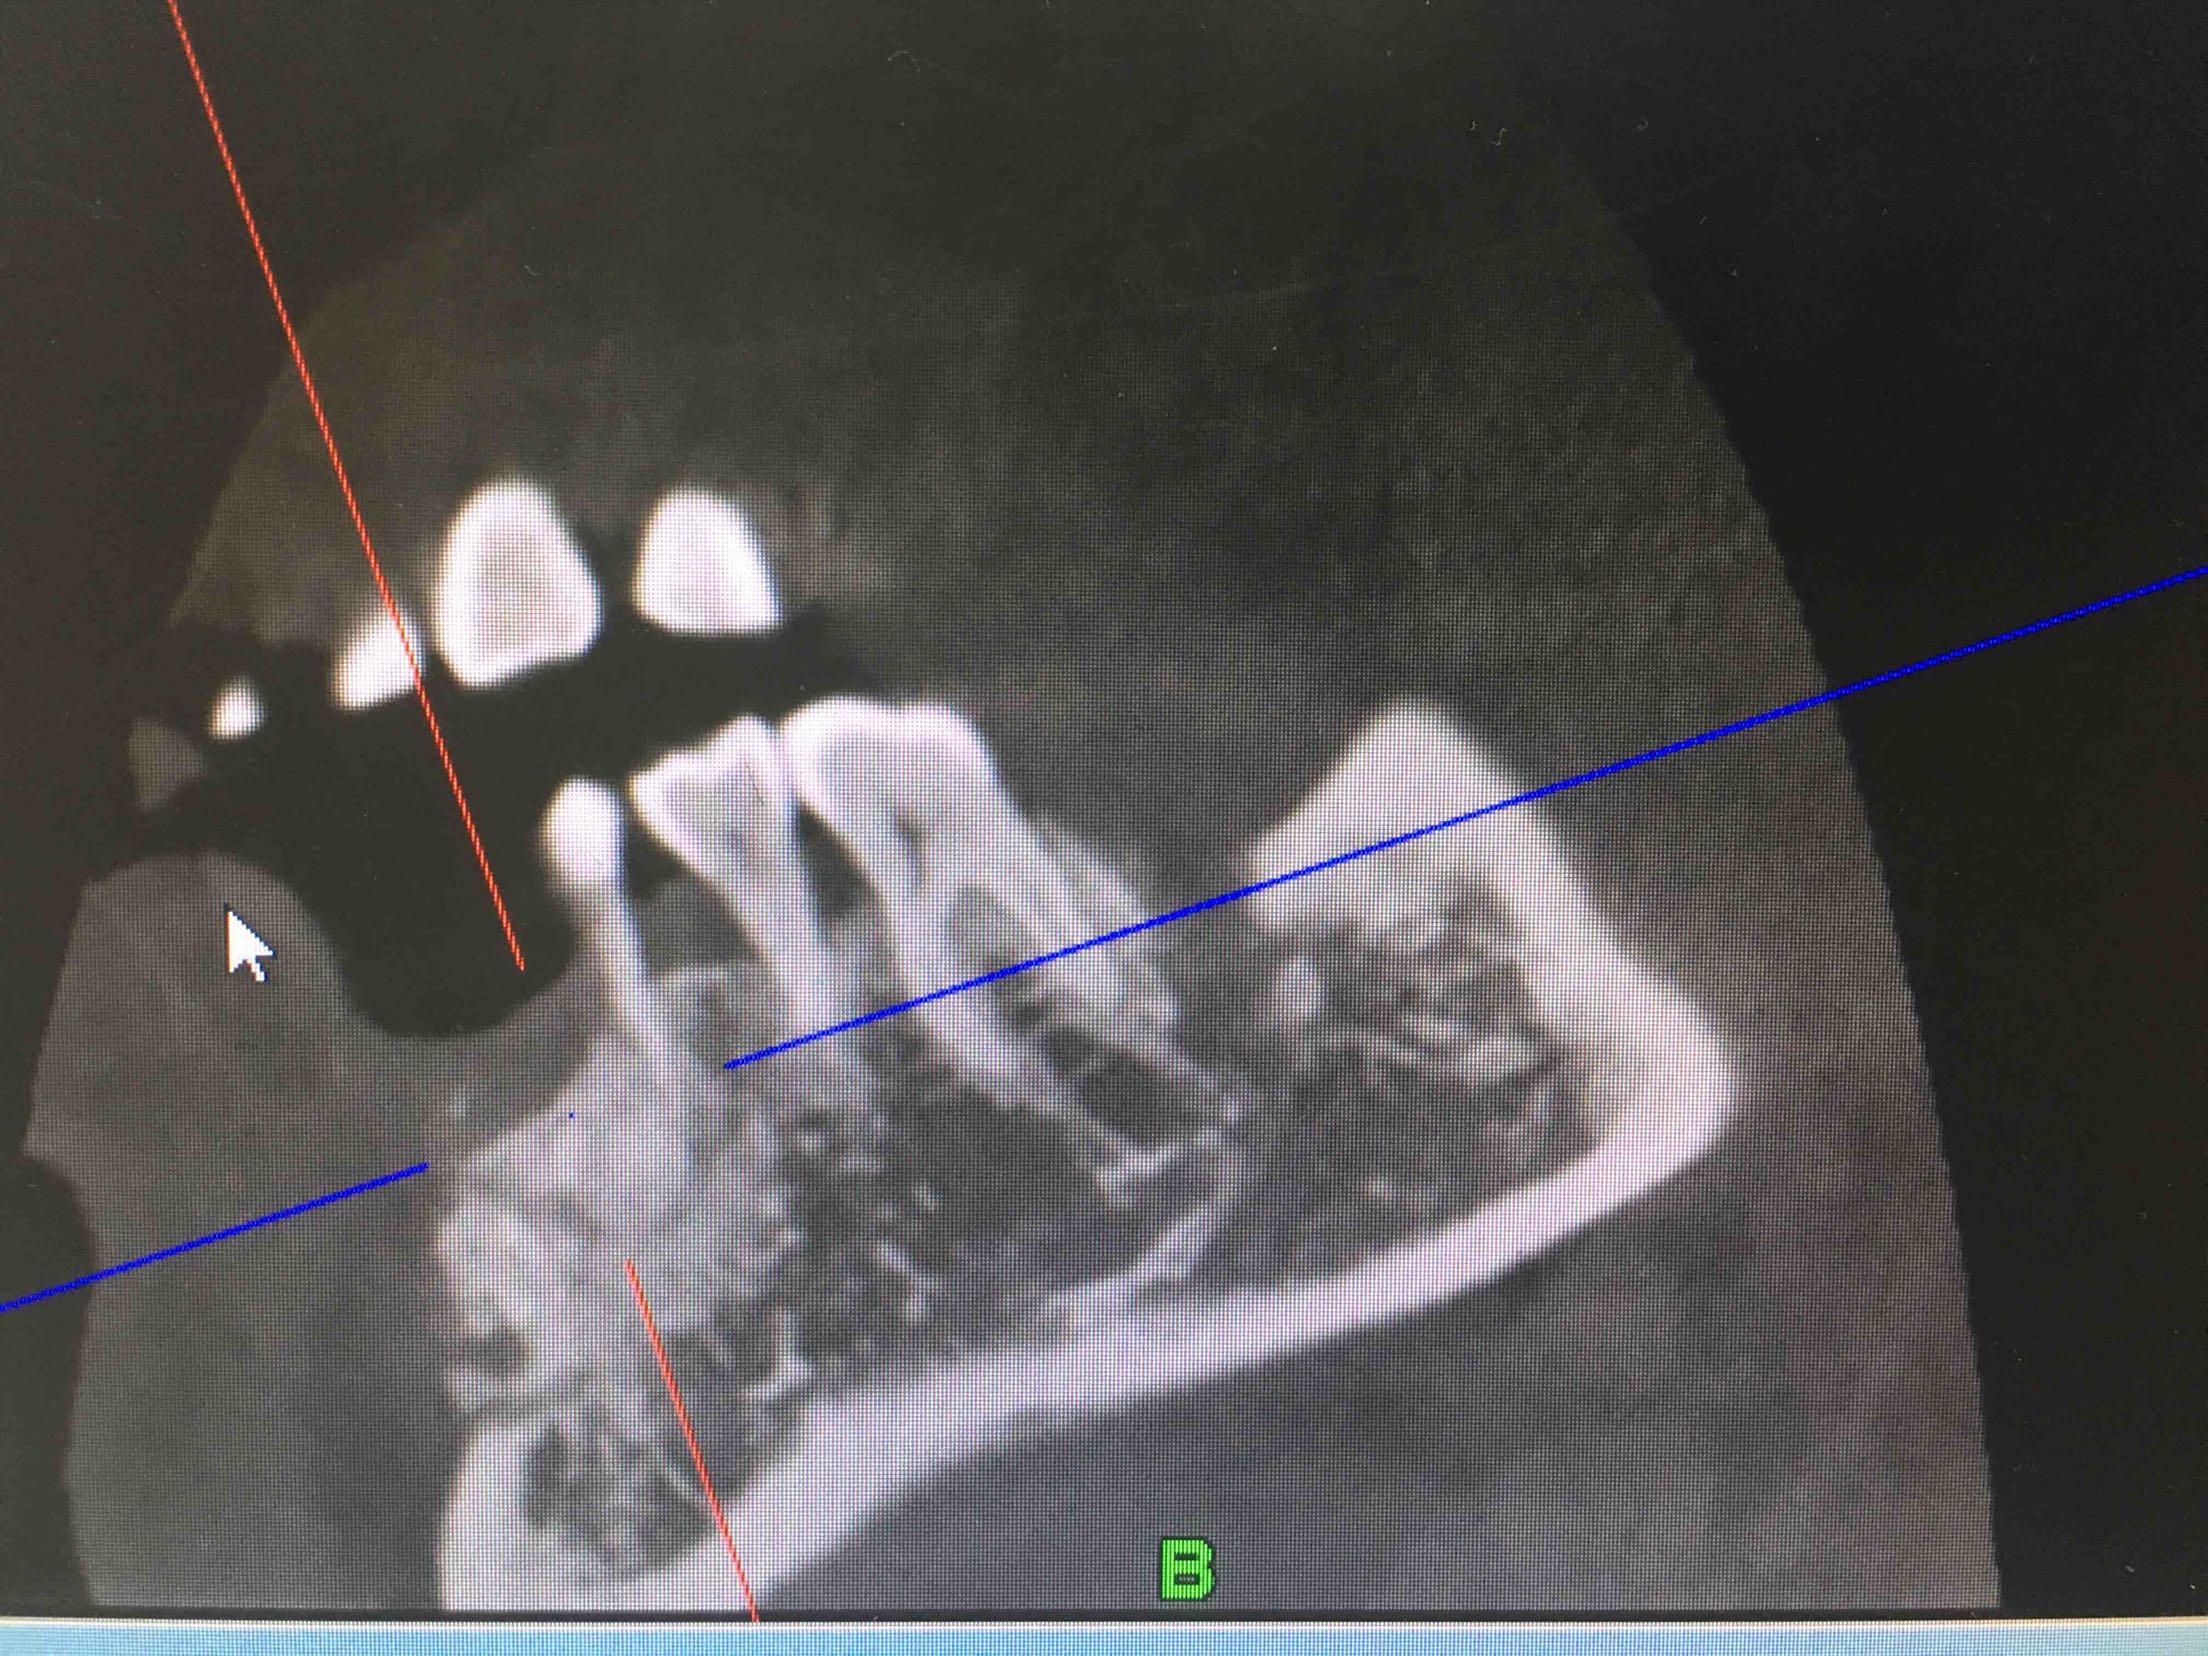

41、43、44牙松动2-3度,42牙缺失,全景片及CBCT显示牙槽骨吸收严重。

两周后,局麻下,翻瓣拔除44牙,在41、42根方环形钻取骨块,钛钉固定于43牙骨缺损处,Bio-ss骨粉0.25g,海奥生物膜,严密缝合!嘱半年后植牙!

植入42、44登腾3.4-10两枚植体